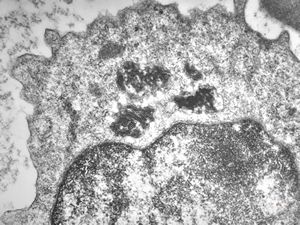

bone marrow - crystalloid inclusions Charcot-Leyden crystals formation

bone marrow - crystalloid inclusions Charcot-Leyden crystals formation v.s.